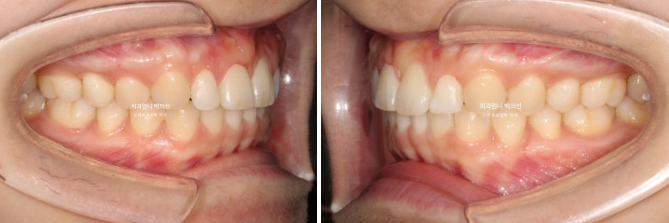

23년 4월에 거미스마일 옥니 과개교합 개선을 위해 내원하신 환자분입니다.

윗니에 덮여 아랫니가 전혀 보이지 않는 심한 과개교합 입니다.

좌우 잇몸의 높이가 다른 잇몸 비대칭도 보입니다.

25.02

좋은 교합입니다.